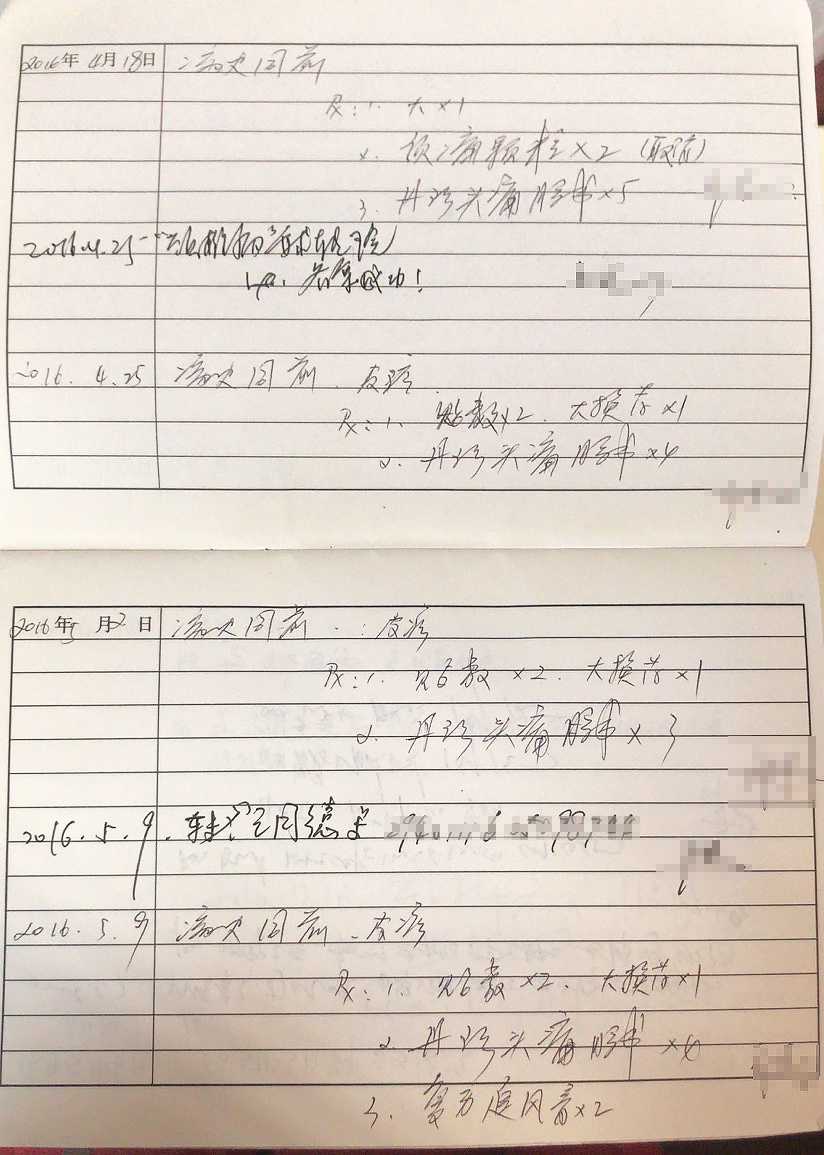

阶级会在一个人的身上留下最深刻的烙印。颈椎病、腰椎间盘突出、腕管综合征等,这一切都向我们表明,实时通讯的自动化社会改造了我们的身体。同样地,如果你的键盘用得足够得久,总有几个键帽会被敲打到面目模糊。键盘作为一个外置化的器官,为我们呈现了在这个技术时代肉眼可见的器官损耗。

现在,我们邀请每一位赛博格,分享你作为赛博格的受损器官图像,我们将以此作为元数据,建立起一个文献档案库。颈椎也好,键盘也罢,都是我们被困在系统里的在场证明。